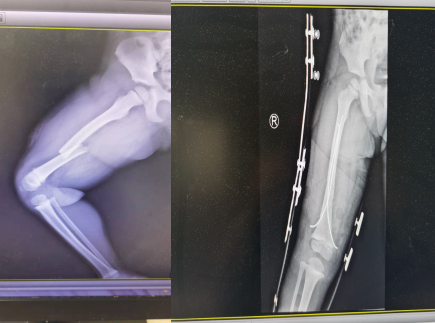

回想事发情形,甜甜妈妈至今心有余悸。3月21日早上,甜甜妈妈因着急送大宝去学校,甜甜此时正在睡觉,就将甜甜独自留家中,送大宝去学校,10分钟不到就回到家。到家后的在房间并未看见甜甜,每个房间都查看一遍后,她把头伸出窗外,瞬间懵了,那二楼的空调外机上趴着的正是她的小女儿。她冲出家门,直奔二楼,并在邻居的帮助下拨打的我院的急救电话。接到消息后,急诊科马上开启绿色通道,并联系外科、ICU、骨一科等科室为女童做好抢救准备。经过仔细的检查,诊断为右股骨干骨折、气胸、左侧髁突骨折、左额锁骨骨折。因患儿年纪小,骨骼尚未发育成熟,骨一科桂春生主任与包仕友医生制定了详细的治疗方案,先固定患肢,择期对右股骨干进行手术治疗,经过半个月的治疗,术后摄片示:骨折复位良好,各髓内钉位置良好,于4月2日出院。